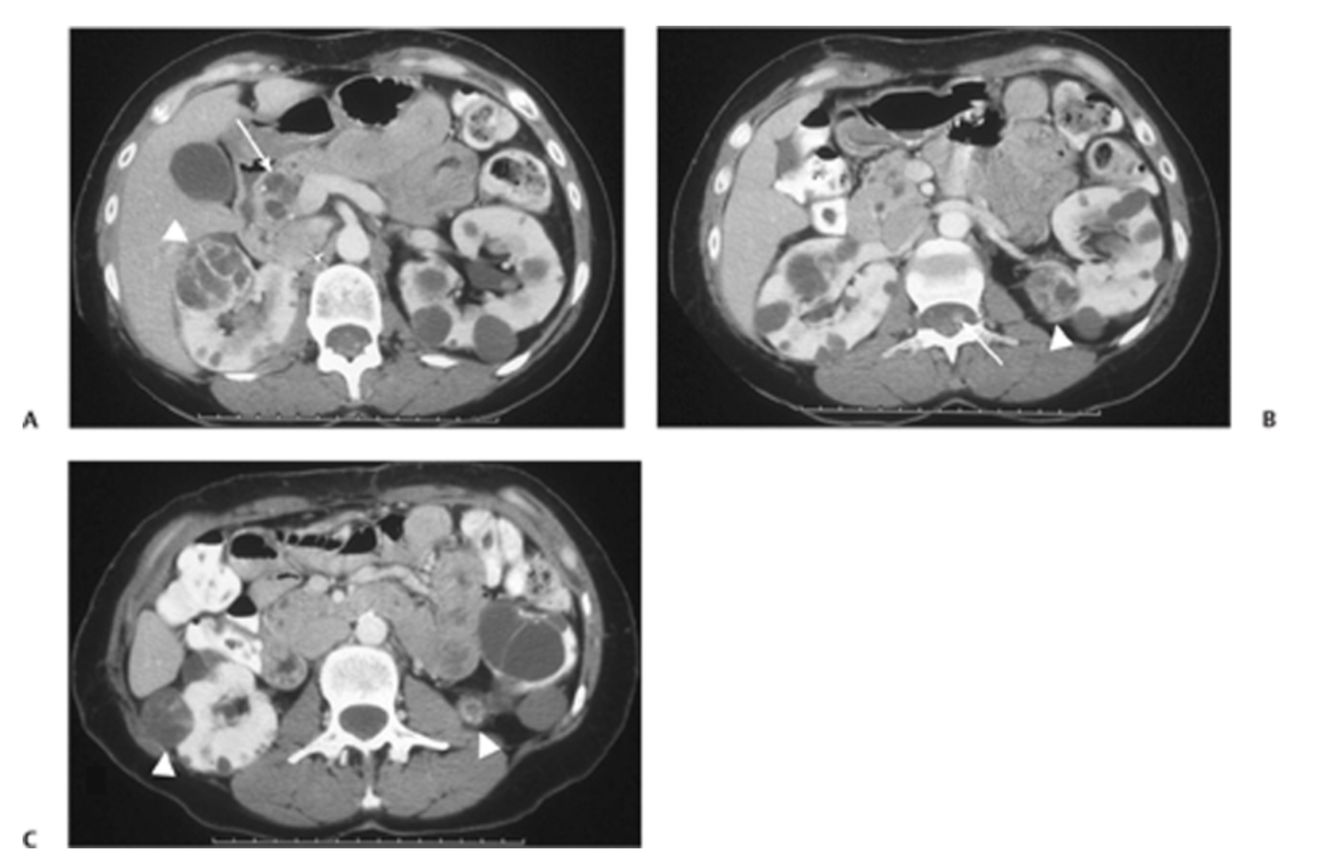

Fig. 63.1 (A) Postcontrast CT image shows bilateral renal cysts. There is a large cyst within the right kidney with thick enhancing septations (arrowhead). Note the multiple pancreatic cysts (arrow). (B) Axial image shows a mixed solid and cystic lesion in the left kidney (arrowhead), along with an enhancing nodule in the chord (arrow). (C)An additional complex cyst with enhancing septation is seen in the right kidney (arrowhead), along with a small enhancing lesion in the left kidney (arrowhead).

Re ADPCKD describe the following:

Type of inheritance?

Genes?

Renal findings?

Associated findings?

AD

PKD1, PKD2

(ciliopathy)

Multiple bilateral variably sized renal cortical and medul-

lary cysts; number and size

of cysts increase with time; nephrolithiasis; chronic kidney disease typically occurs in late adulthood

Ductal plate malformations (eg, congenital hepatic fibrosis); extrarenal cysts (eg, liver, pancreas, seminal vesicles); intracranial aneu- rysms (typically in adult- hood)